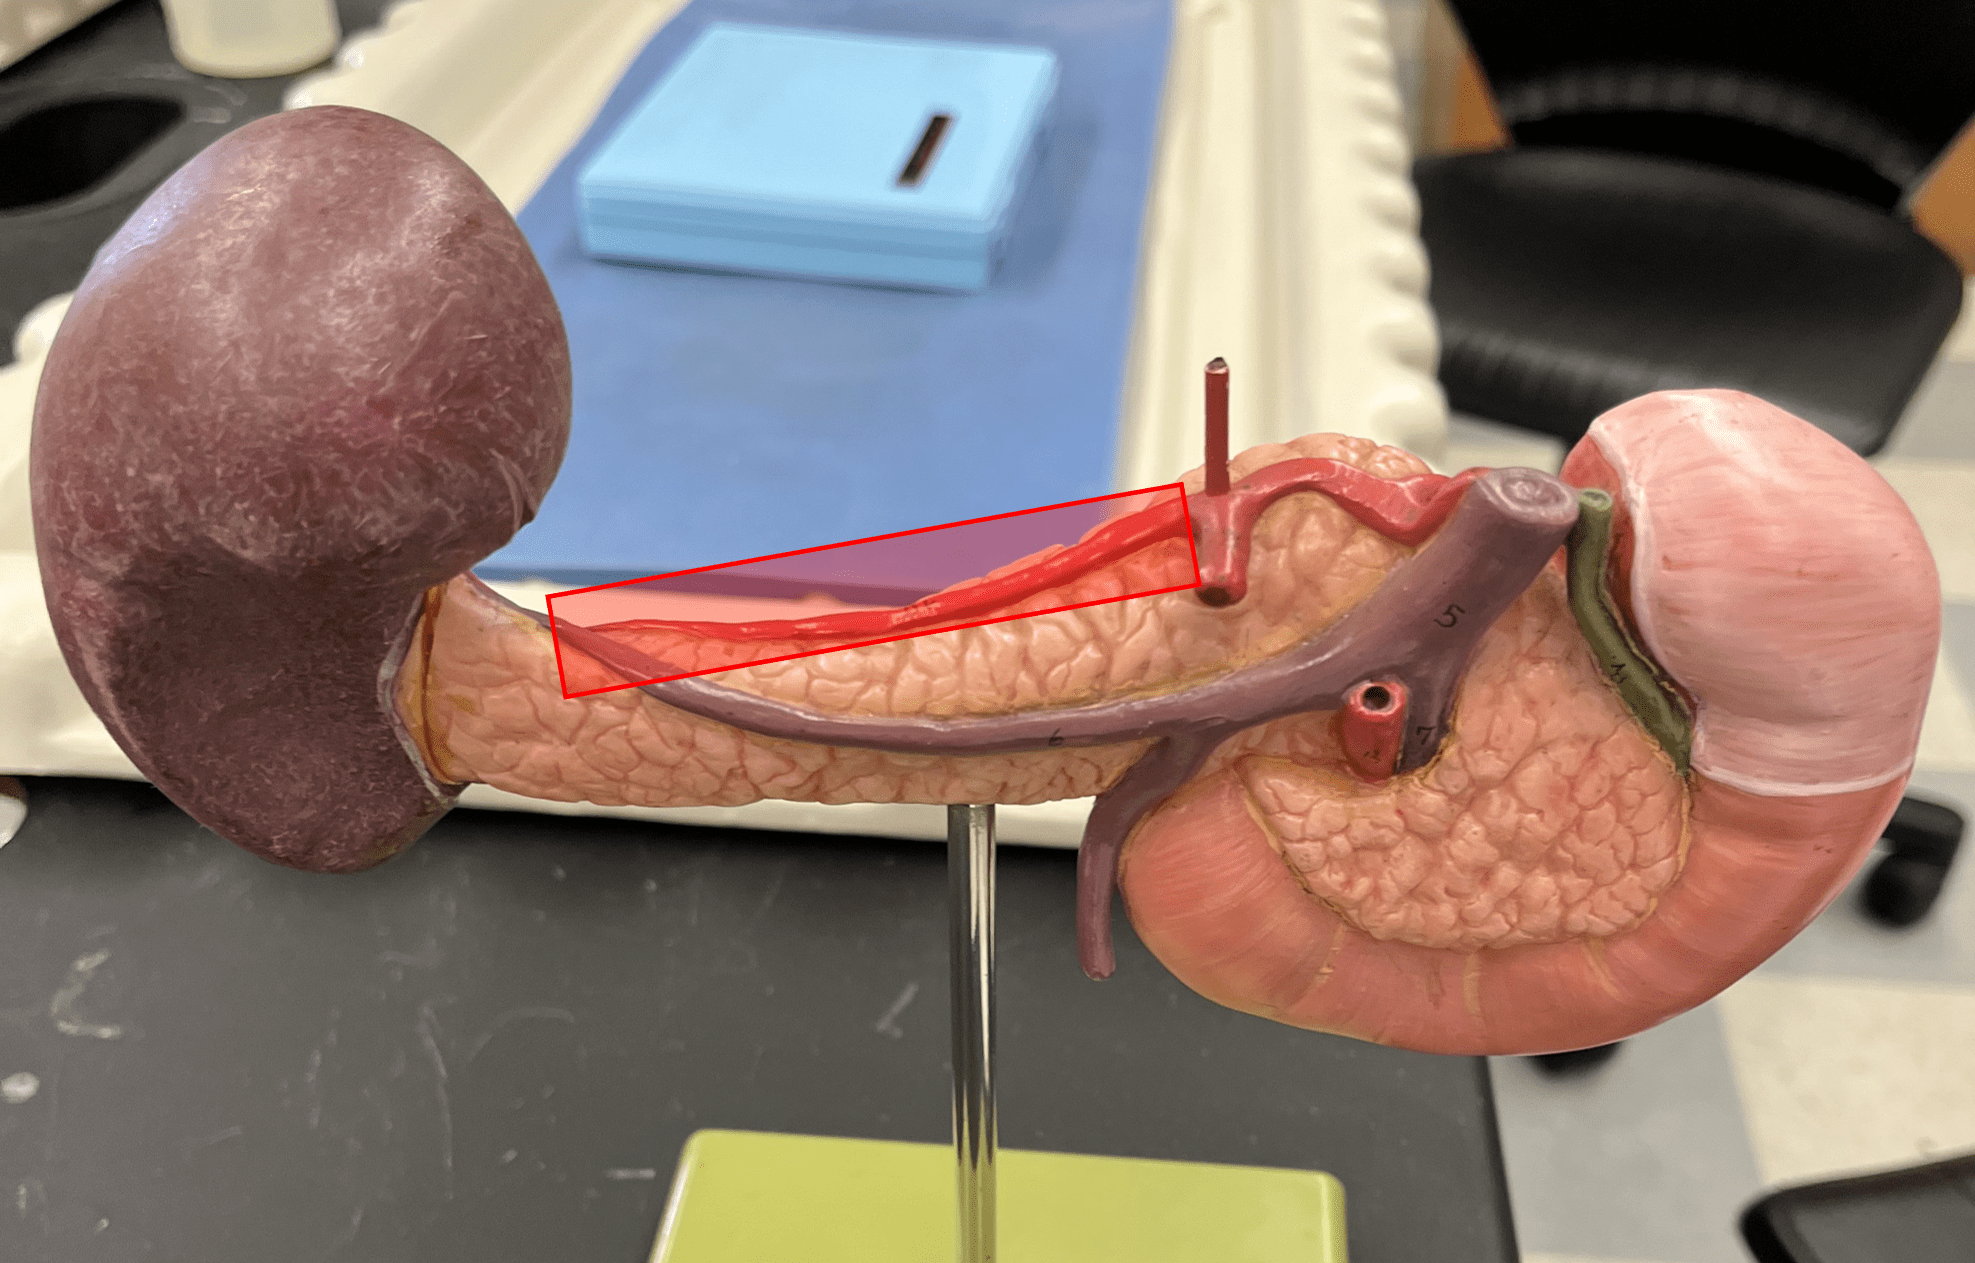

• Also known as the tunica adventitia.

• Composed of loose connective tissue and collagen fibers.

New cards

• A thin layer of elastic connective tissue.